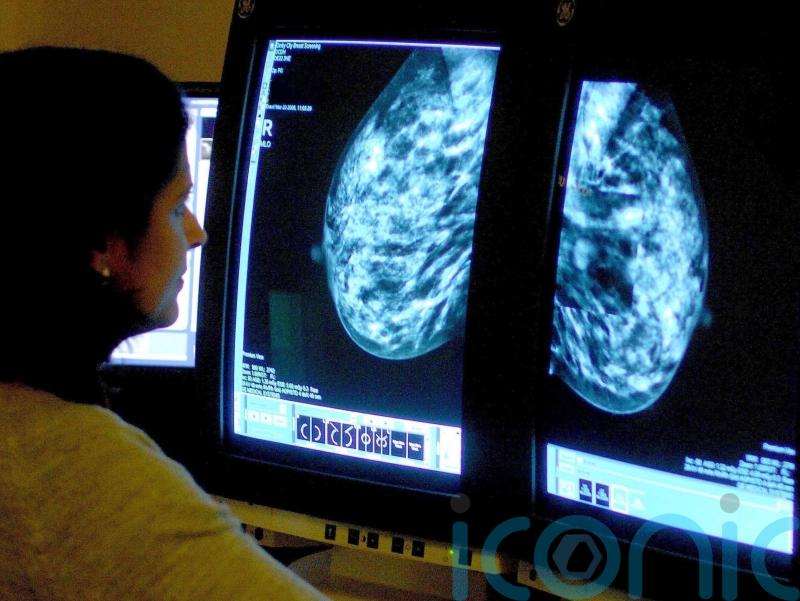

The importance of red flag referrals and screening routes for early diagnosis of cancer to improve survival rates for people in Northern Ireland has been highlighted in a report.

The study from the Northern Ireland Cancer Registry (NICR) at Queen’s University Belfast used research conducted on patients diagnosed between 2018 to 2020.

The Routes to Diagnosis report shows a strong relationship between a patient’s route to diagnosis and how advanced their cancer was at diagnosis.

The report found higher proportions of patients diagnosed with early-stage disease came through screening or red flag referral routes, with a higher proportion with advanced (late-stage) disease coming from emergency presentation.

The data showed that one-year survival was 87% for those diagnosed via red flag referral compared with 42% for those diagnosed following emergency presentation, and more than 98% of those diagnosed via screening are alive one year after diagnosis.

It also found that the two years from diagnosis to survival ranged from 33% for those diagnosed via an emergency presentation route to 80% for those diagnosed through a red flag referral route.